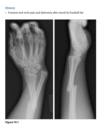

A 21-year-old man with worsening pain in the left wrist after an injury 6 months earlier (Fig. 2.13.1).

Figures 2.13.2 and 2.13.3 are of a 46-year-old man with wrist pain

Anteroposterior view of the left wrist

(Fig. 2.13.1) shows an ulna that is shorter than the

radius (i.e., negative ulnar variance or ulnar minus

variance) and a lunate that is sclerotic and some-

what irregular in shape.

Kienböck disease (i.e., lunatomalacia)

Kienböck disease, or lunatomalacia, is

osteonecrosis of the lunate. It is most common in

­ patients 20 to 40 years old and has a predilection

for the dominant hand in individuals involved

in manual labor.

Cause unknown

shortened ulna

in relation to the radius (i.e., negative ulnar variance

or ulnar minus variance) is seen in up to 75% of pa-

tients with lunatomalacia and is considered a major

cause of the disorder

The imaging findings, which do not always corre-

late with the patient’s symptoms, include increased

density or sclerosis of the lunate and, eventually, alteration in the normal bony shape with collapse

on radiographs.

For example, in a 46-year-old

man with wrist pain, a coronal T1-weighted image

(Fig. 2.13.2) demonstrates low signal intensity in

the lunate (arrow) and negative ulnar variance. The

gradient-recalled echo MR image (Fig. 2.13.3) shows

the signal intensity within the lunate to remain low

(arrow). These features are diagnostic of osteone-

crosis (i.e., Kienböck disease). Surgical intervention

includes lunate replacement, radial shortening, and

ulnar lengthening.